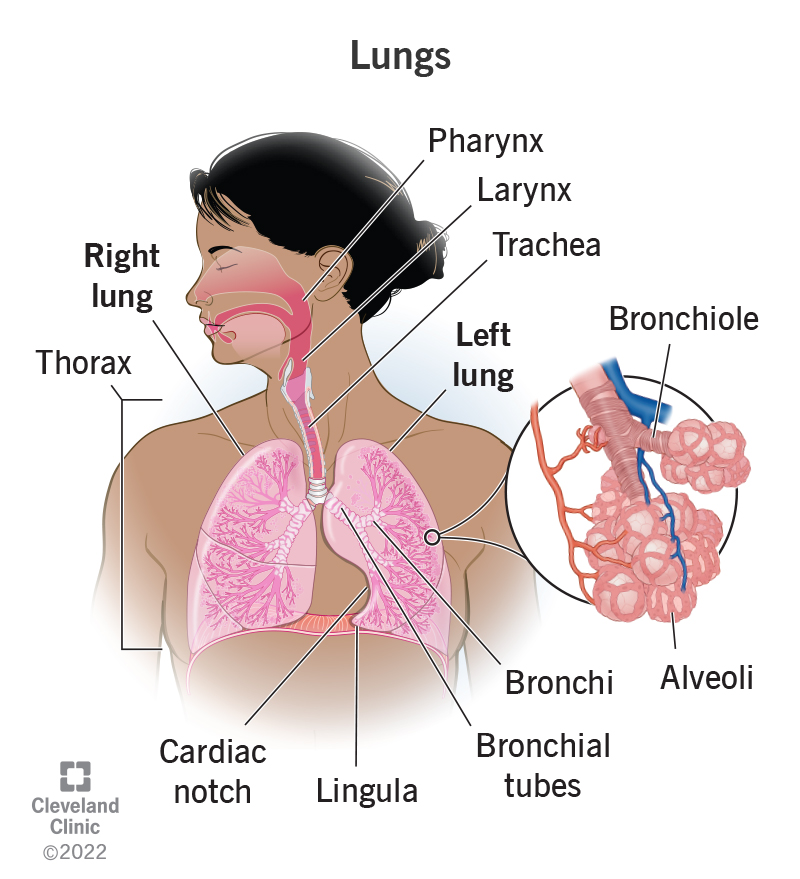

Lung Anatomy & Function - Lung Nodule, Lung Disease And Lung Infection

healthjade.com

healthjade.com

alveoli lung lungs gas exchange pulmonary anatomy alveolus membrane blood structure respiratory function microscopic supply infection disease

Anatomy Of The Respiratory System - Health Encyclopedia - University Of

www.urmc.rochester.edu

www.urmc.rochester.edu